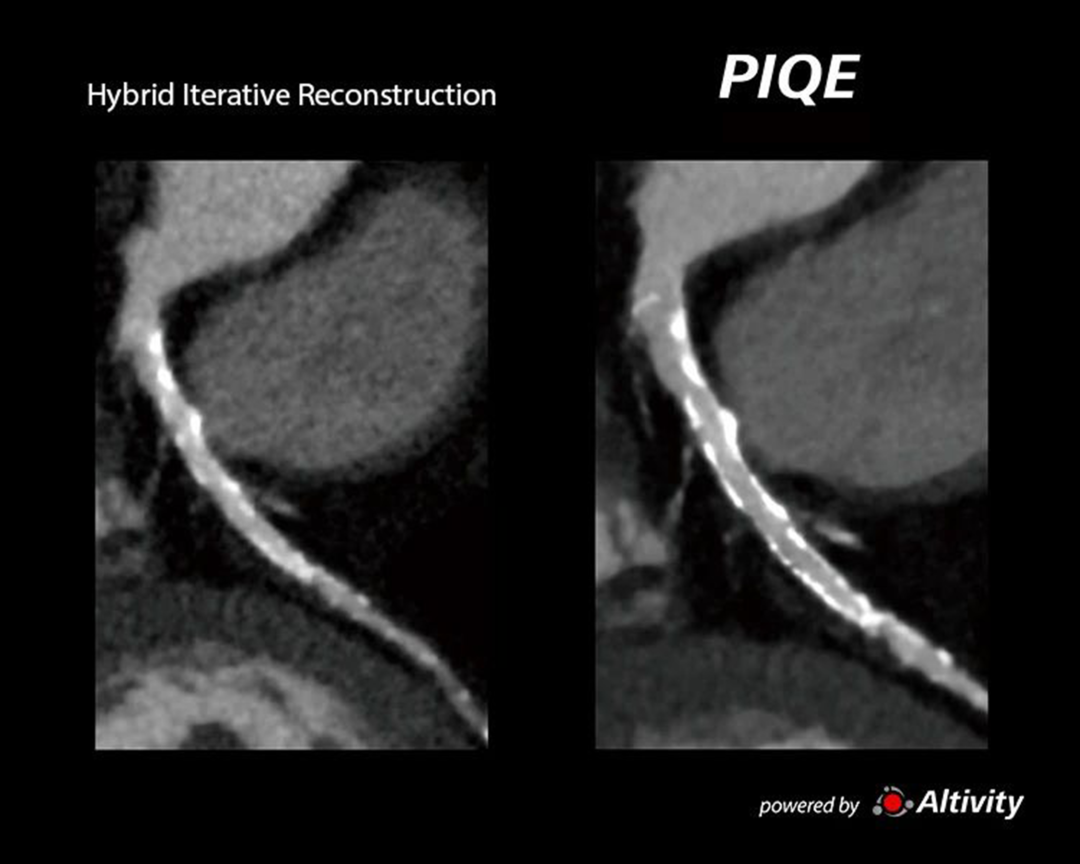

PIQE for CT

突破传统心脏成像限制

对分辨率的追求驱动着CT技术的进一步发展。一方面是聚焦硬件的探测器革新,例如0.25mm的超薄探测器切割、光子计数探测器等;另一方面,则是通过图像重建算法的辅助来实现,例如从传统的FBP到迭代算法、再到如今的深度学习重建算法。而佳能医疗将AI图像技术与宽体探测器深度融合,将CT图像分辨率提升至了新高度。

基于佳能医疗的深度学习神经网络平台,结合Aquilion Precision 4K级高清数据采集平台进行训练,得到高清AI引擎PIQE。结合宽体CT平台,PIQE可以同时提升图像分辨率和覆盖宽度,实现任意心率及心律不齐下的高清心脏成像,尤其有利于对心血管支架和斑块的显示。